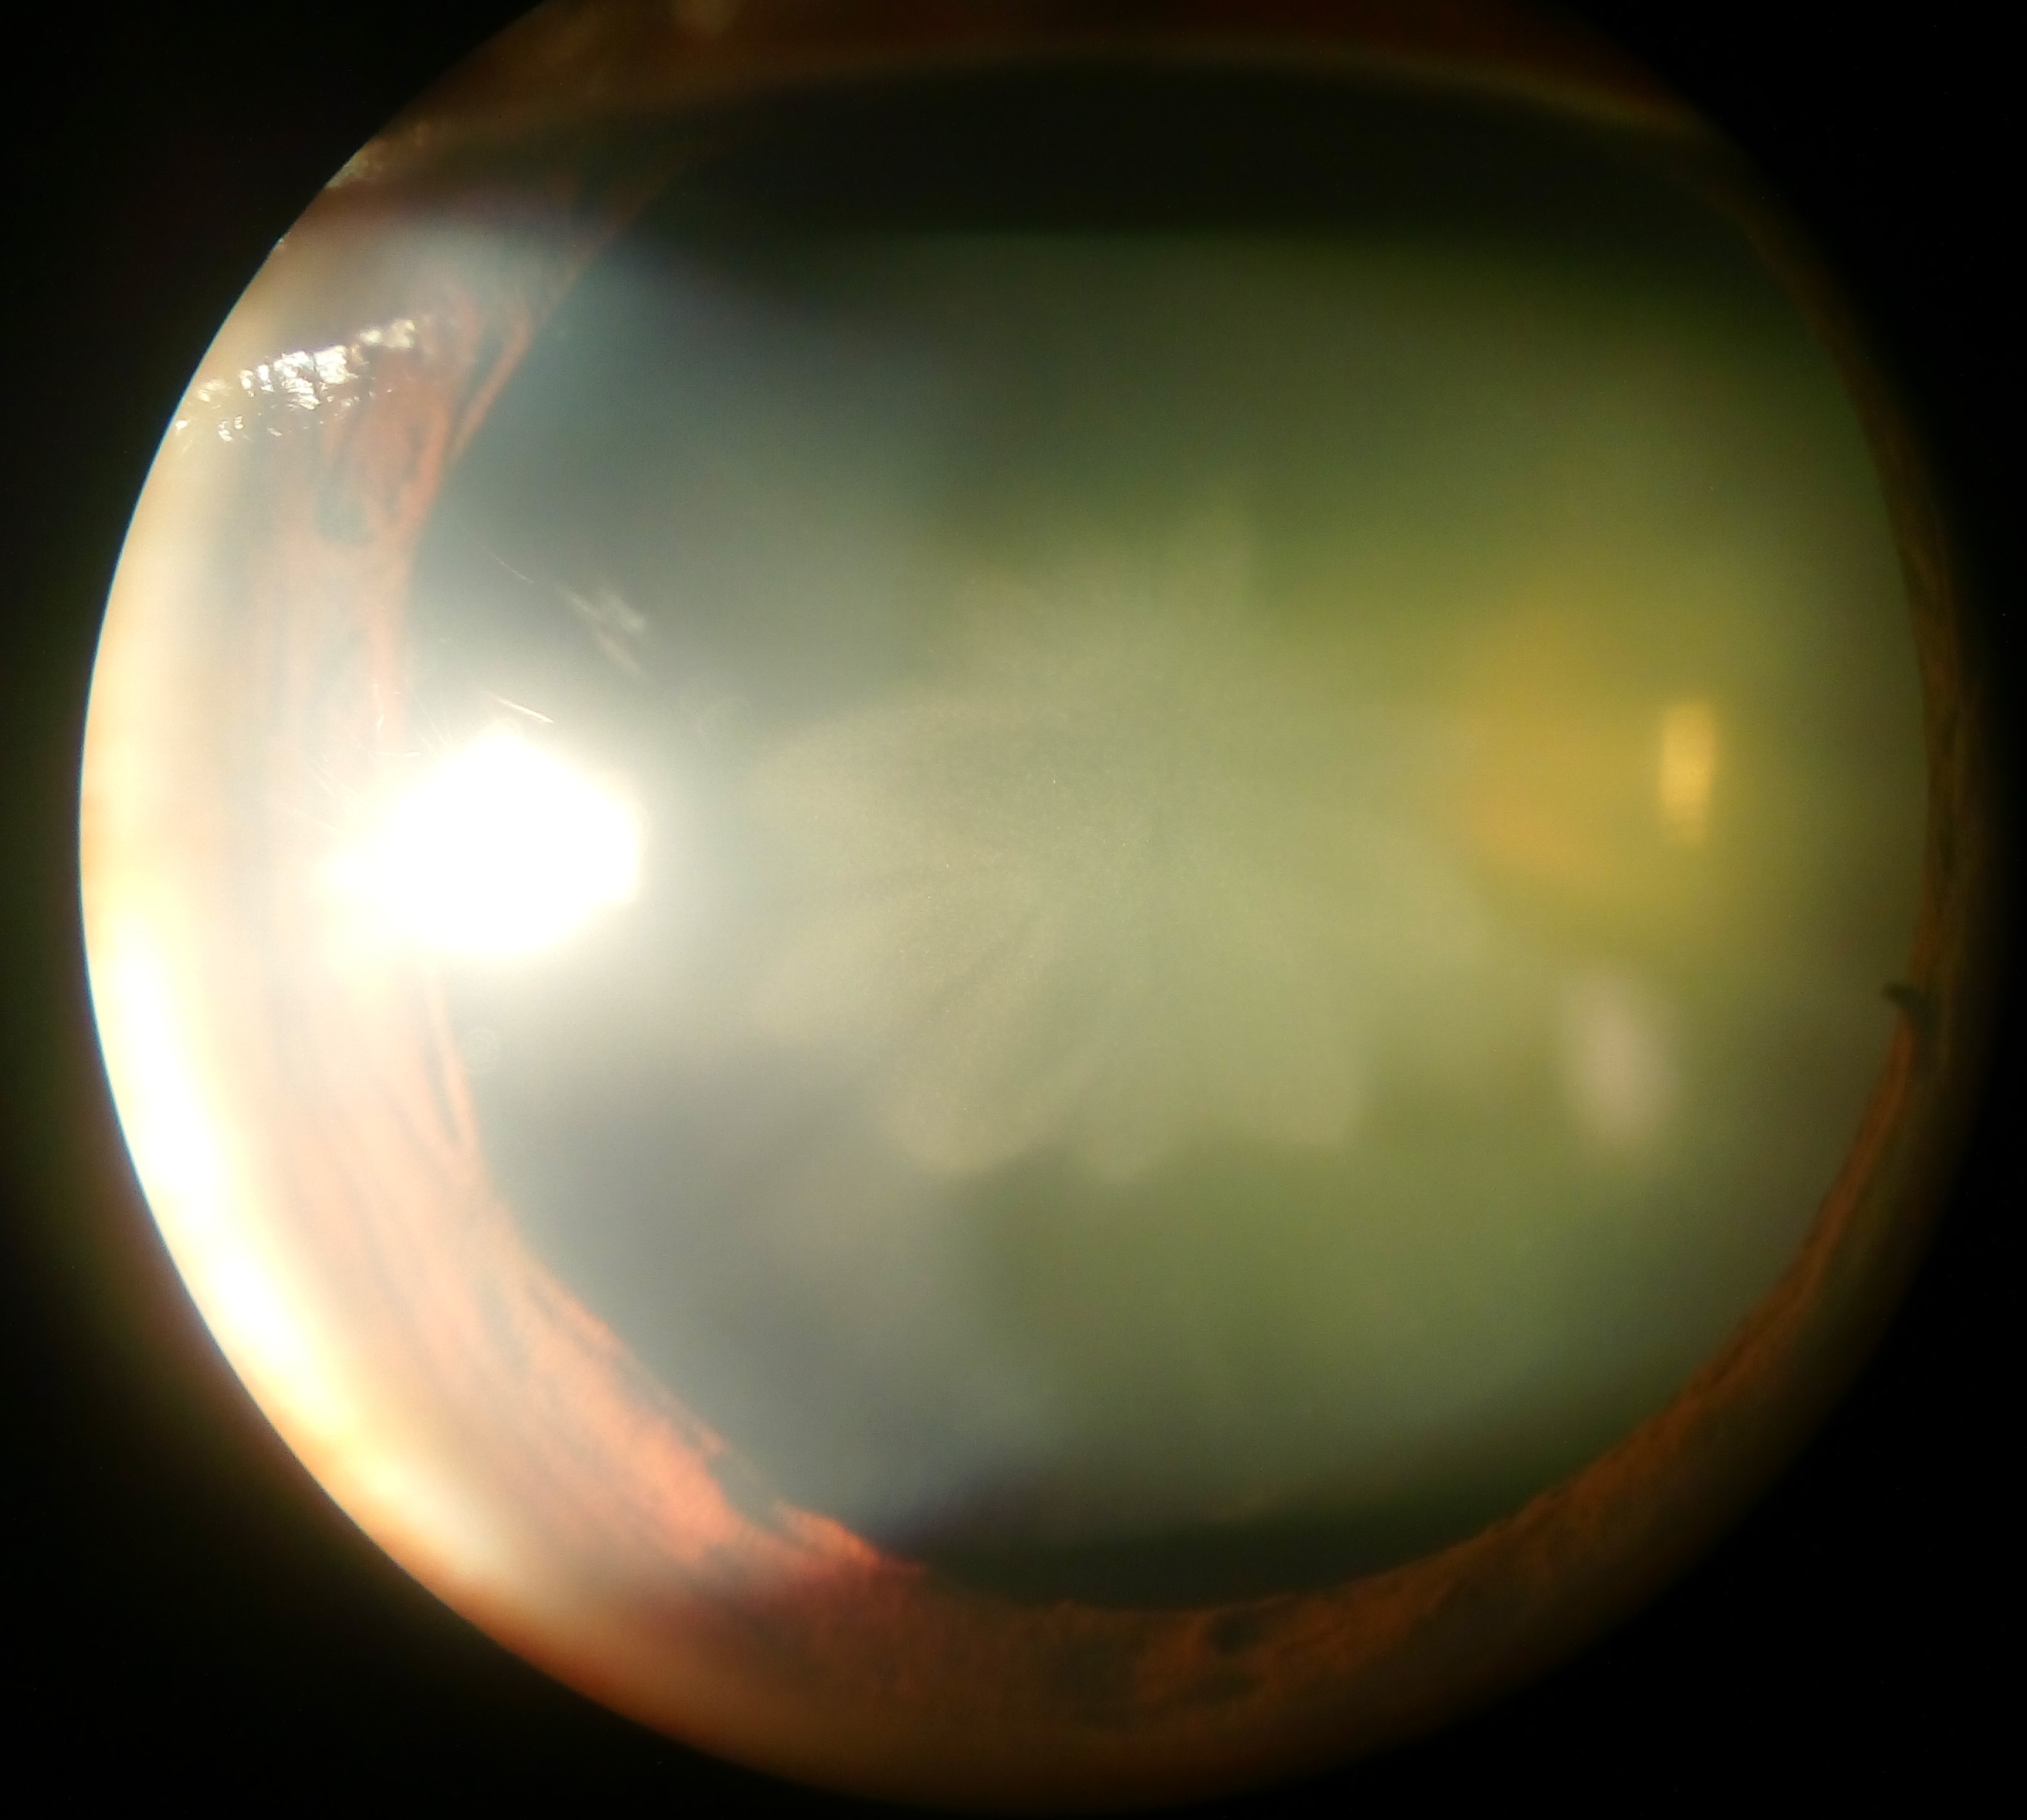

백내장은 눈의 수정체가 혼탁해져 시력 저하를 유발하는 질환이다. 주요 증상으로는 시력 저하, 흐릿함, 눈부심 등이 있으며, 핵경화, 피질, 후낭하 백내장 등 유형에 따라 증상과 진행 속도가 다르다. 원인은 선천성과 후천성으로 나뉘며, 나이가 가장 흔한 원인이고 외상, 방사선, 유전, 흡연, 약물 등 다양한 요인이 영향을 미친다. 백내장은 시력 검사, 세극등 검사 등을 통해 진단하며, 수술을 통해 혼탁해진 수정체를 제거하고 인공수정체를 삽입하는 것이 일반적인 치료법이다. 수술 후에는 후발 백내장, 망막 박리, 안구내염 등의 합병증이 발생할 수 있다. 백내장은 전 세계 실명의 주요 원인 중 하나이며, 자외선 차단, 항산화 물질 섭취 등을 통해 예방할 수 있다.

- 백내장이 진행됨에 따라 눈의 동공이 백색 또는 노란색으로 변함

증상은 백내장의 유형에 따라 다르지만 상당 부분 겹치는 경우도 있다. 핵 경화성 또는 갈색 백내장이 있는 사람들은 종종 시력 감소를 경험한다. 핵 백내장은 일반적으로 근거리 시력보다 원거리 시력 장애를 더 크게 유발한다. 후낭하 백내장이 있는 사람들은 주요 증상으로 눈부심을 호소하는 경우가 많다.[14]

백내장은 시력 검사로 백내장 형성의 심각도를 파악할 수 있다.[14] 다른 안 질환이 없는 경우, 백내장 진단은 주로 시력 검사를 통해 이루어진다. 세극등 검사를 통해서도 백내장을 진단할 수 있는데, 수정체 불투명도 분류 시스템(LOCS III)을 사용하여 백내장을 핵, 피질, 후낭하 유형으로 분류할 수 있다. 또한 이 시스템은 백내장을 1~5의 척도로 심각도에 따라 추가로 분류할 수 있으며, LOCS III 시스템은 재현성이 매우 높다.[45]